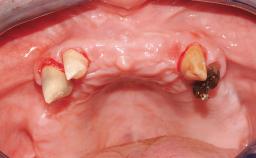

Immediate Loading of Eight Implants in the Maxilla and Six Implants in the Mandible and Final Restoration with Three-Unit and Four-Unit FDPs

Extensive scientific evidence has confirmed that immediately loaded implants with fixed full-arch provisional restorations can osseointegrate with success rates similar to conventionally or delayed loaded implants. A number of immediate-provisionalization techniques for edentulous jaws have been described. Some protocols differ when it comes to prefabricated provisional templates versus complete denture conversion; intrasurgical impressions versus direct relining; and cemented versus screw-retained provisional restorations. In this context, complete-denture conversion has been proposed for either intrasurgical impressions or direct relining. Another possibility is the utilization of a prefabricated provisional to be adapted either in the mouth (by direct relining) or in the laboratory (on a working model obtained from an intrasurgical impression).